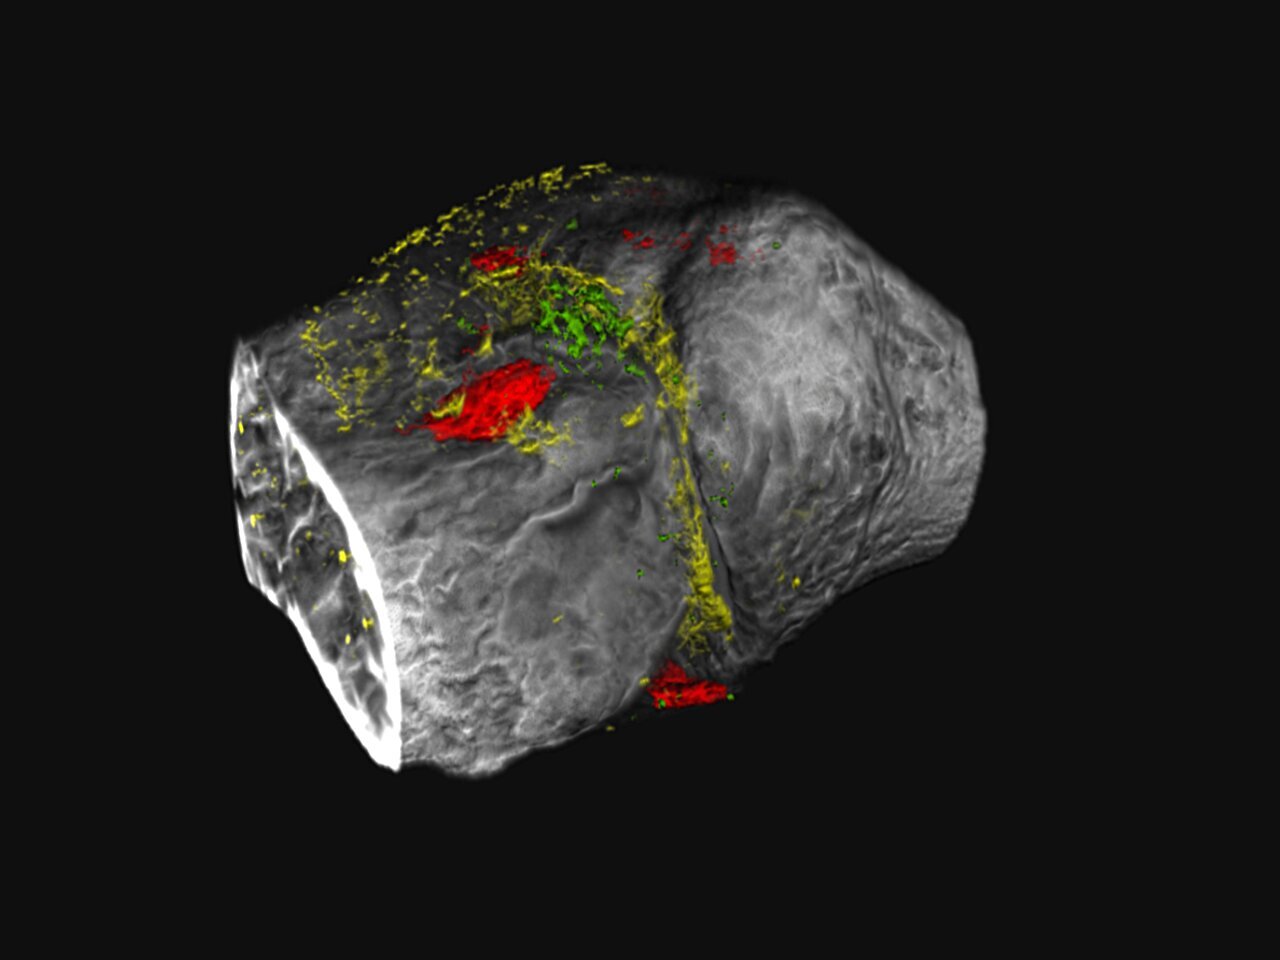

Ученые из Университета штата Пенсильвания разработали новую методику медицинской визуализации, которая позволяет отслеживать прогрессирование остеоартрита — дегенеративного заболевания суставов — в цвете. Используя новые контрастные агенты, они смогли выделить два белка, связанных с этим заболеванием.

Ранее рентгеновские снимки и компьютерная томография (КТ) давали лишь черно-белые изображения, но теперь, благодаря технологии K-edge и фотонно-счетной КТ, врачи могут наблюдать за отдельными биологическими процессами в цвете. Это позволяет увидеть скрытые изменения в тканях задолго до появления клинических симптомов.

По словам Ниветхи Гунасеелан, одной из авторов исследования, новая методика важна для раннего вмешательства при остеоартрите, что может значительно улучшить качество жизни пациентов. С помощью фотонно-счетной КТ ученые разработали нано-пробы, которые связываются с белками агреканом и агреканазой в хрящах, что помогает отслеживать состояние заболевания.